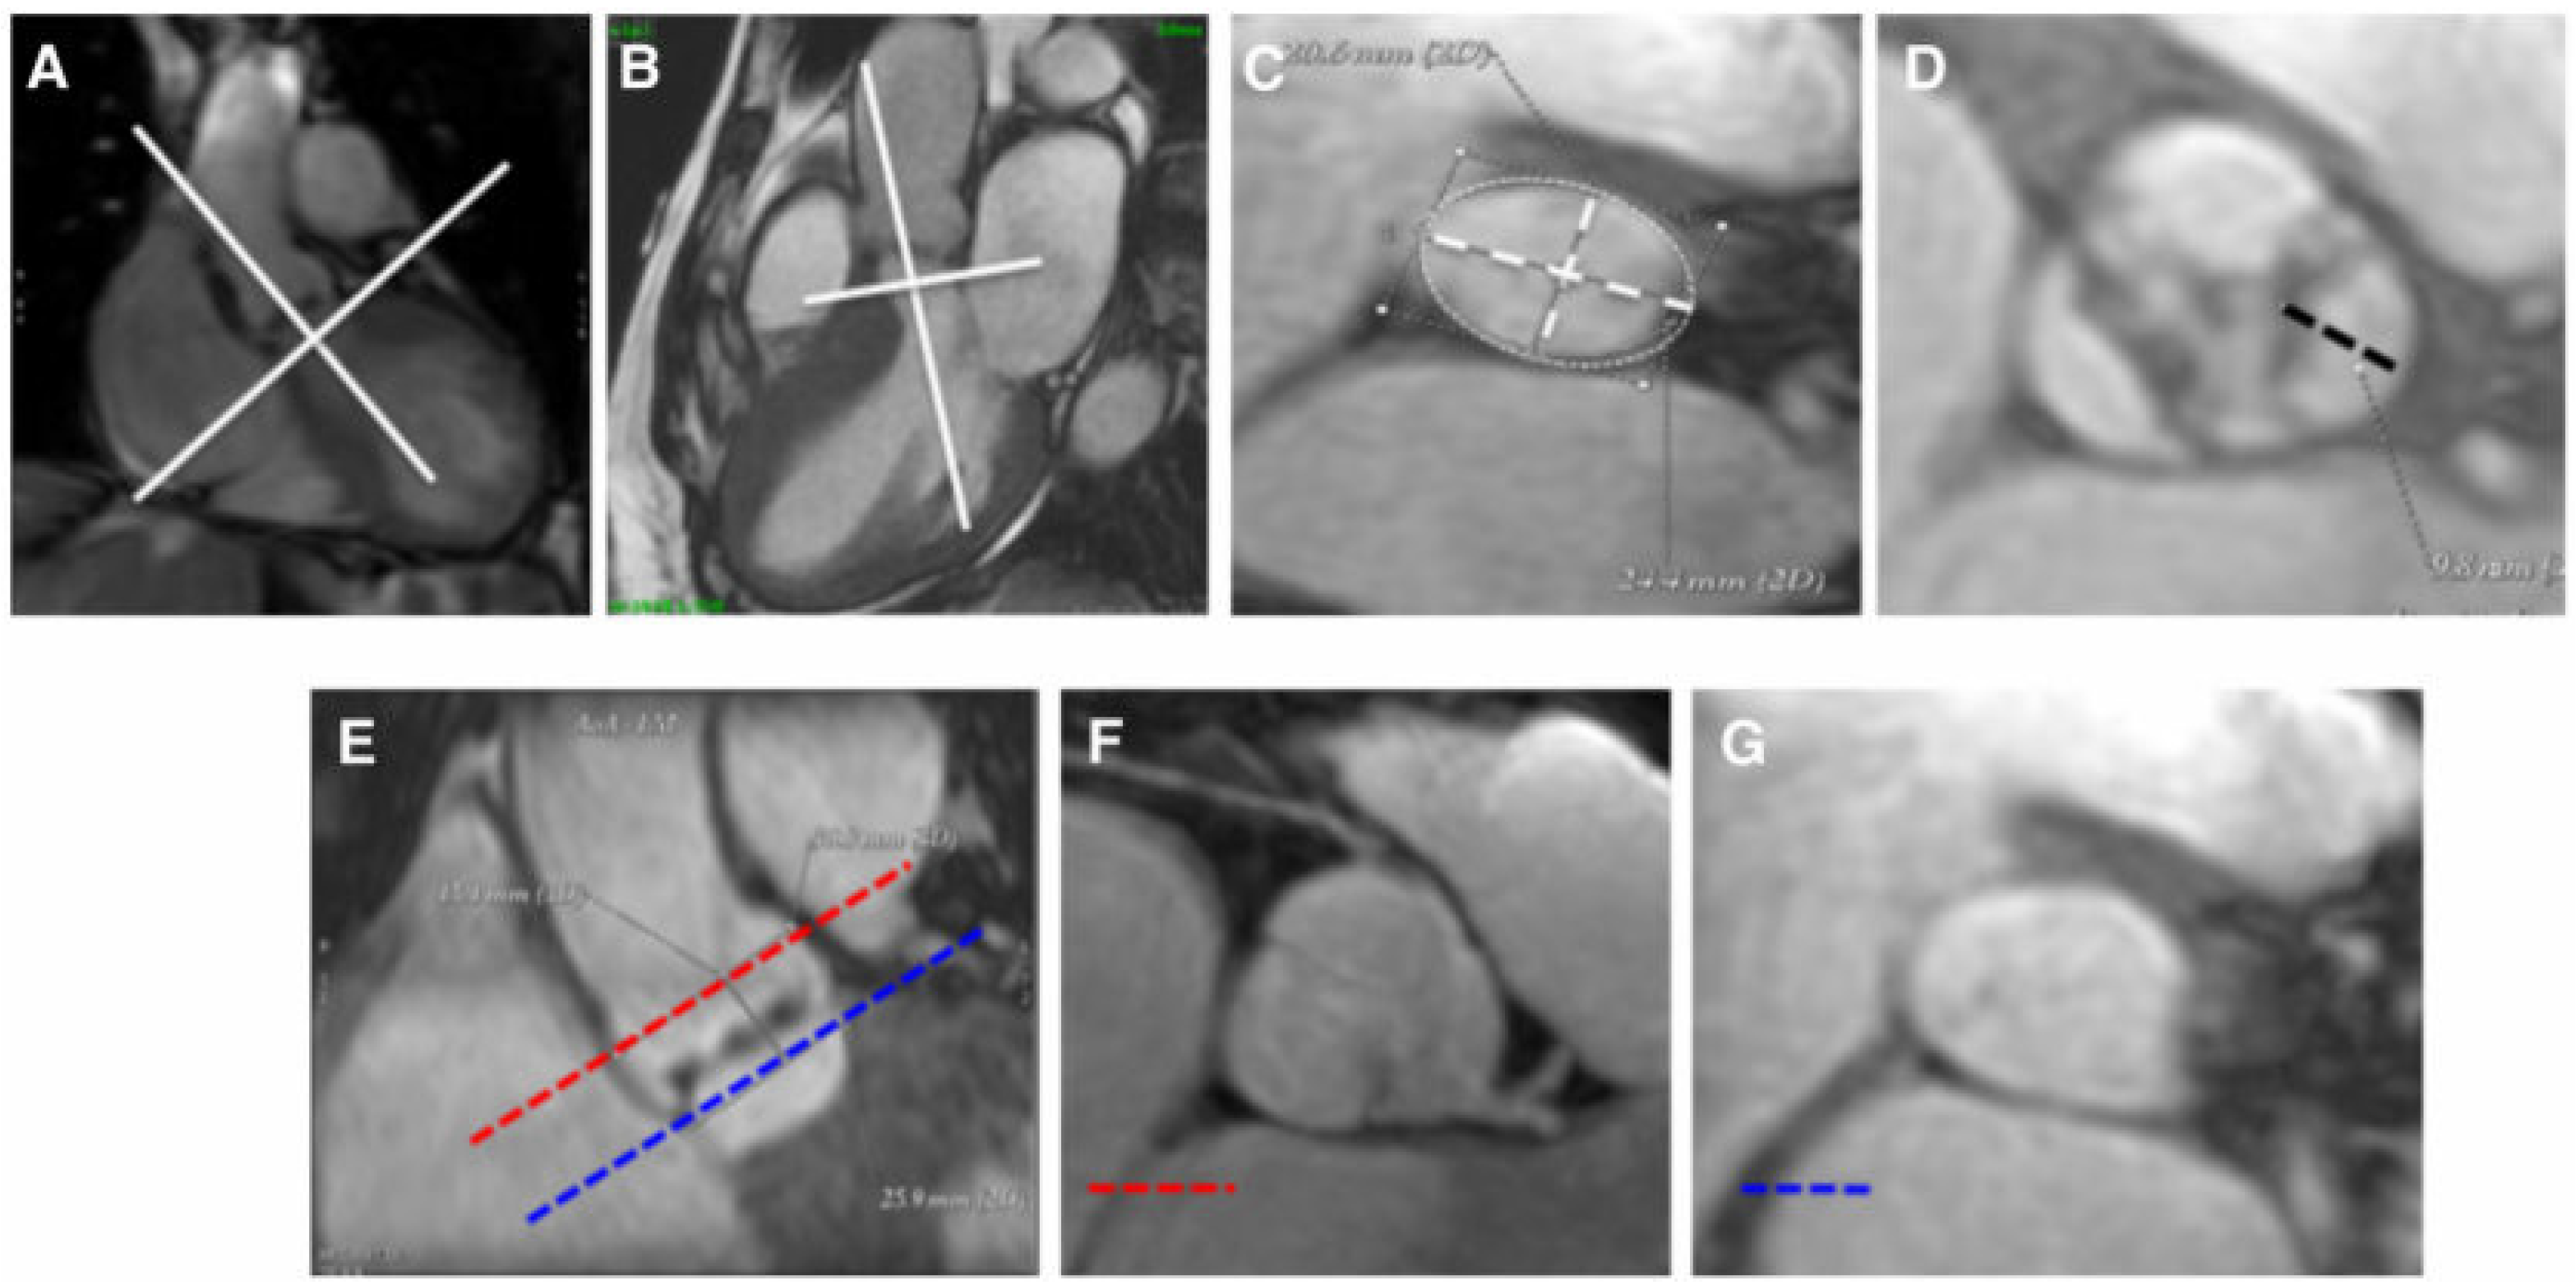

- Pontone, G.; Andreini, D.; Bartorelli, A.L.; Bertella, E.; Mushtaq, S.; Gripari, P.; Loguercio, M.; Cortinovis, S.; Baggiano, A.; Conte, E.; et al. Comparison of accuracy of aortic root annulus assessment with cardiac magnetic resonance versus echocardiography and multidetector computed tomography in patients referred for transcatheter aortic valve implantation. Am. J. Cardiol. 2013, 112, 1790–1799. [Google Scholar] [CrossRef] [PubMed]